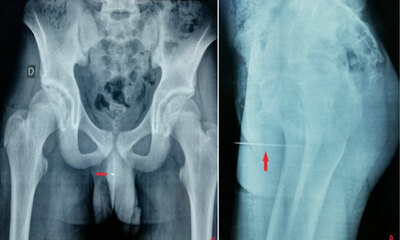

Il s’enfonce une aiguille dans l’urètre et n’arrive plus à la retirer

Le faits divers du jour est assez wtf ou un adolescent qui n’arrivait plus à uriner s’est rendu chez le médecin. Honteux, il explique avoir enfoncé une aiguille 9 cm dans l’urètre pour la stimulation érotique que cela lu...